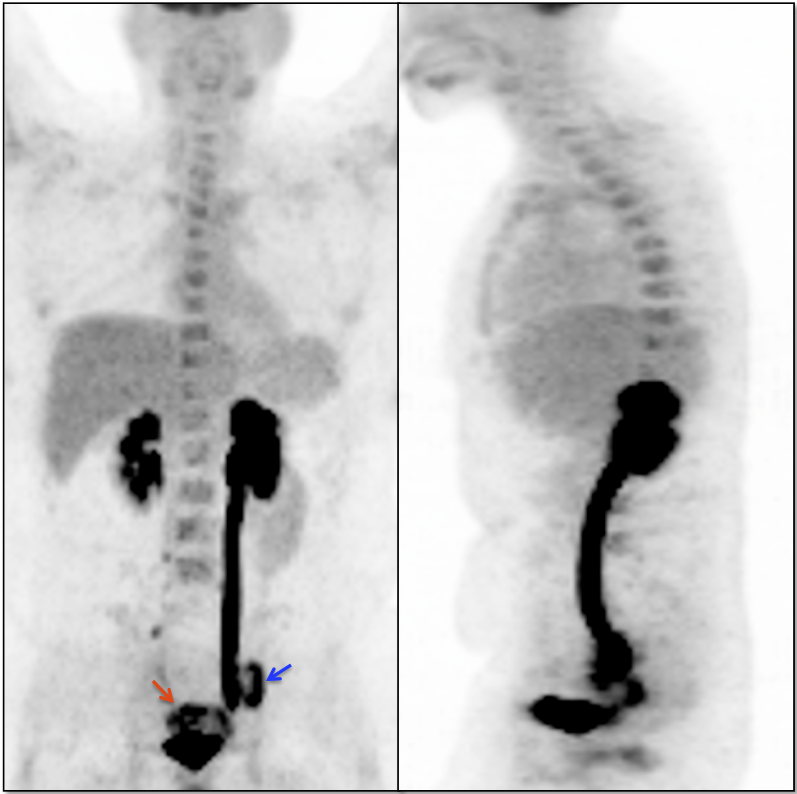

Recurrence, Restaging & Surveillance:

• PET/CT is utilized for patients with known or suspected recurrent disease (or at high risk for recurrence).

• Distinguishing recurrence from post-therapeutic inflammation.

Metastatic Disease:

• Direct invasion of adjacent structures.

• Lymphatic spread to pelvic and retroperitoneal lymph nodes.

• Hematogenous spread, often to lungs, liver, and bone.

False Negatives:

• Primary lesions < 8.0 mm (beneath the resolution of PET)

• Nodes or metastatic deposits < 8.0 mm